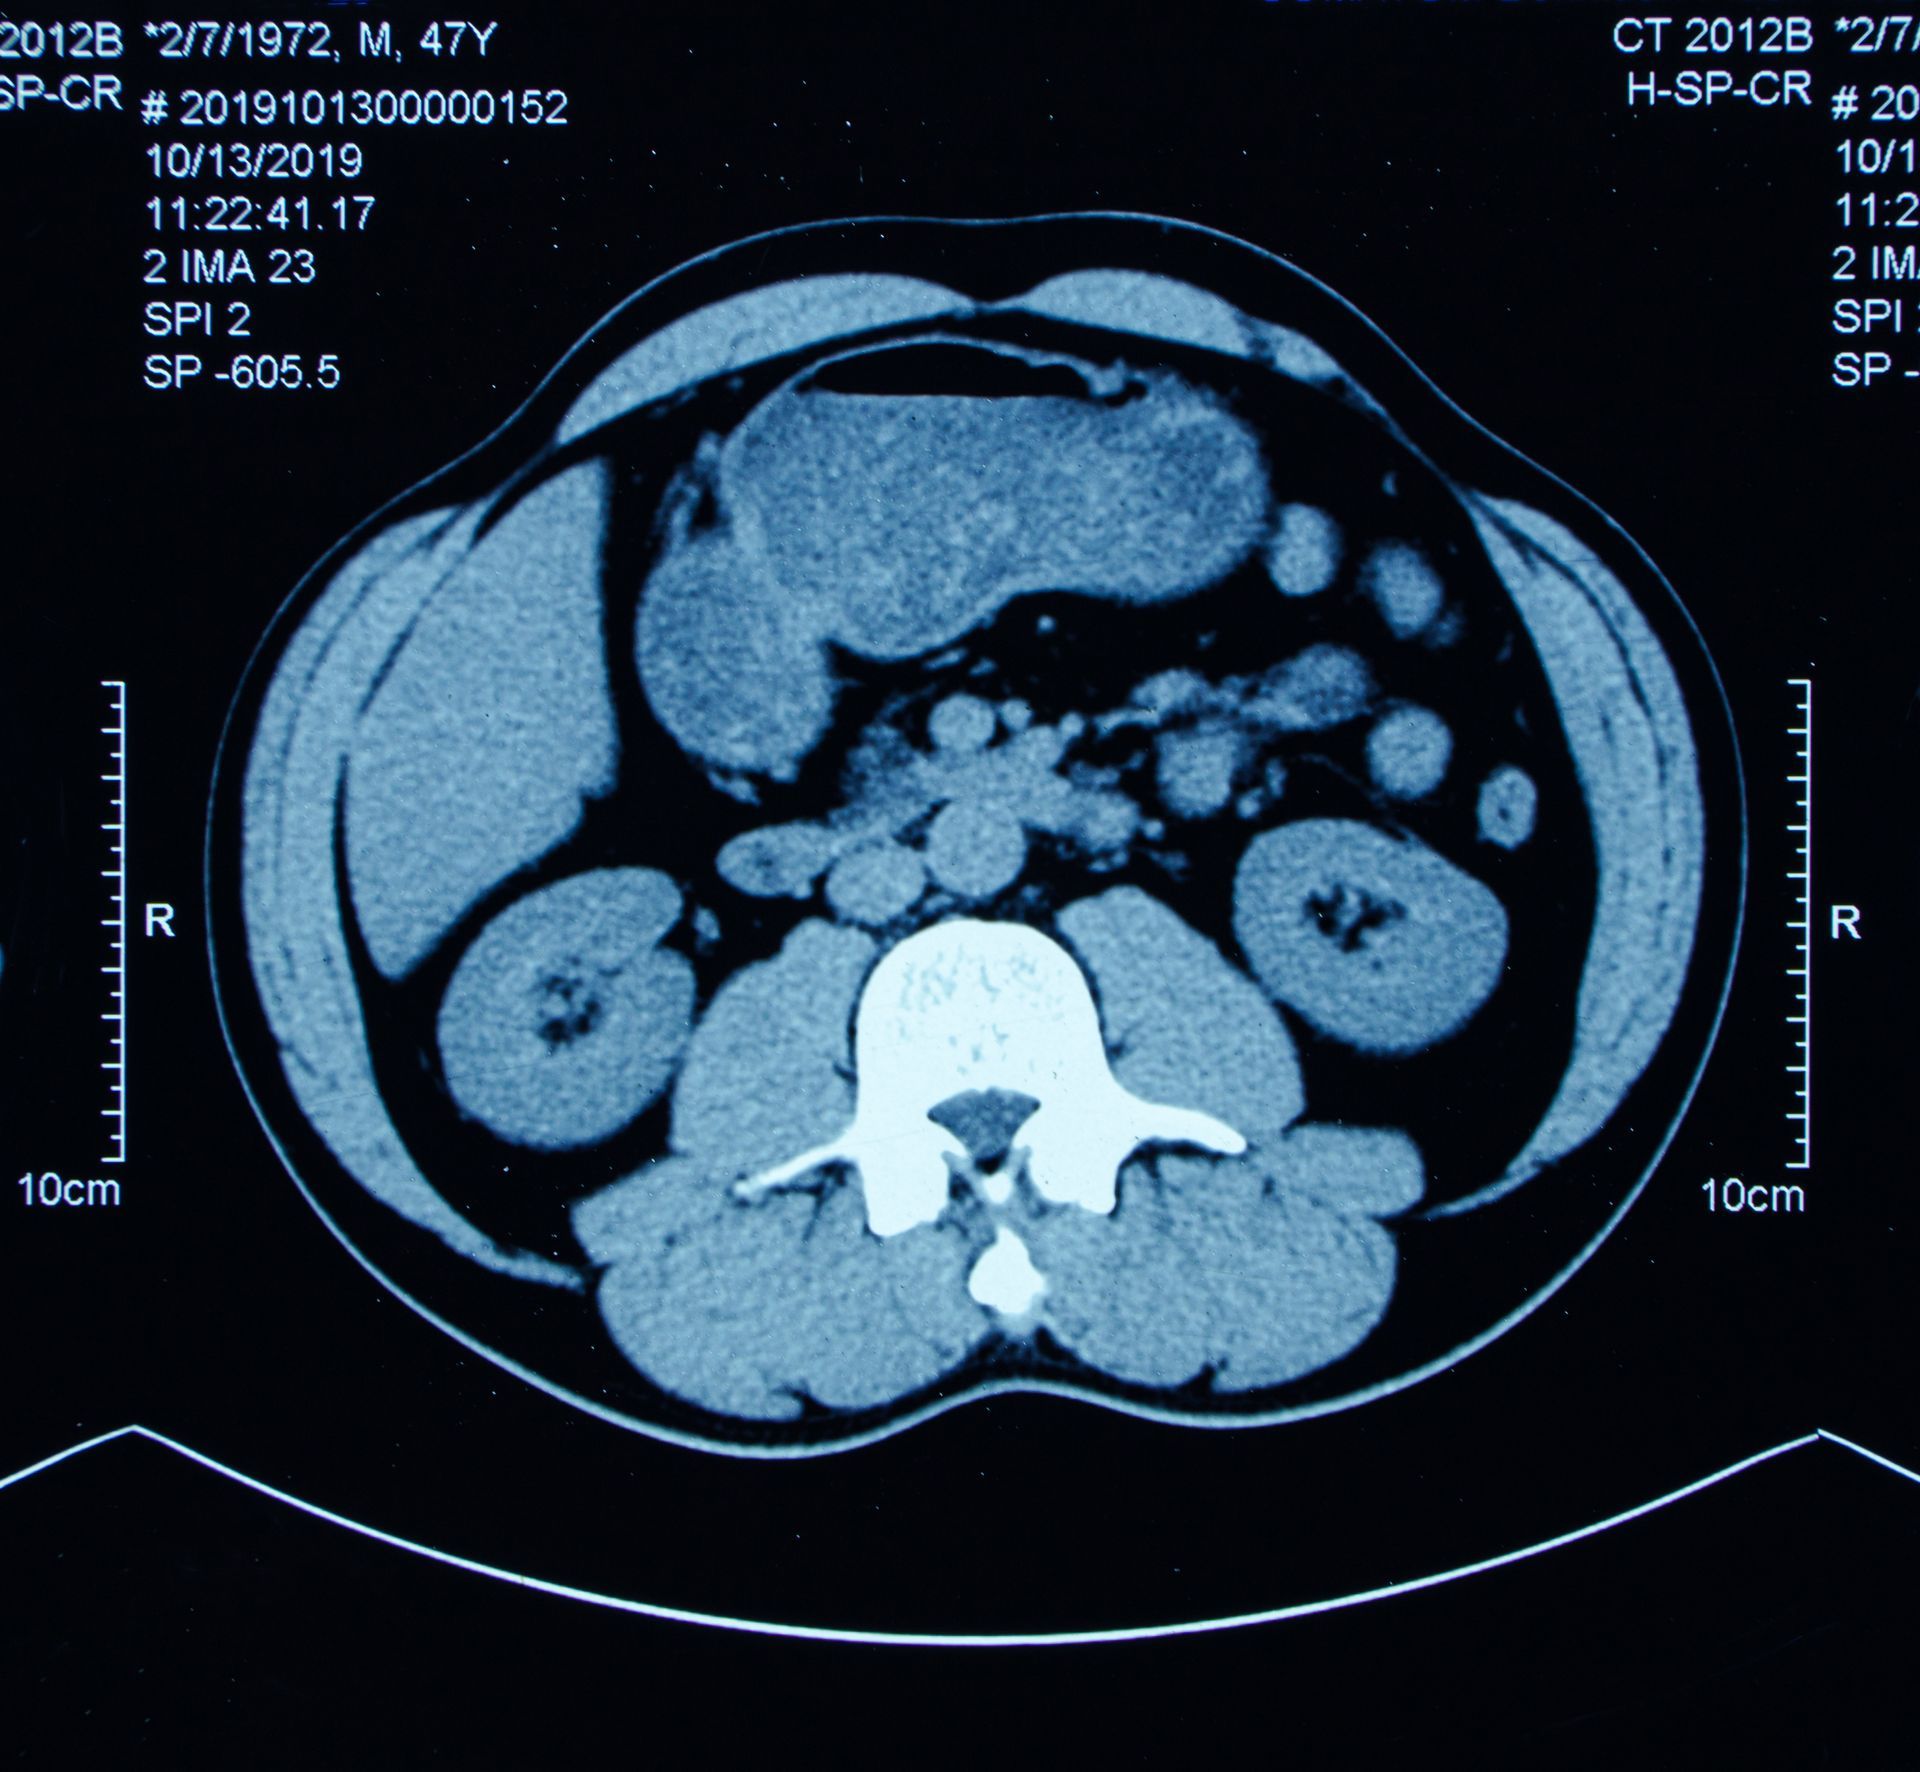

La risonanza magnetica è un esame estremamente versatile e si presta a valutare numerosi distretti corporei con un alto livello di precisione. Viene utilizzata per diagnosticare condizioni neurologiche, patologie a carico delle articolazioni, lesioni muscolari, malattie dell’addome e del bacino, oltre a rappresentare un importante strumento nell’imaging vascolare.

La risonanza magnetica a Casarano (LE) comprende un sistema a 1,5 Tesla, una tecnologia considerata un riferimento nel campo della diagnostica per immagini. Si tratta di un’apparecchiatura ad alto campo dotata di magnete semipermanente che consente lo studio di diversi apparati, sia con sia senza mezzo di contrasto. La potenza del campo magnetico permette di ottenere immagini nitide e dettagliate, utili soprattutto in ambiti come la neurologia, la colonna vertebrale, le articolazioni e gli organi interni.

Questa configurazione ad alto campo garantisce una risoluzione superiore rispetto ai sistemi di livello inferiore, offrendo risultati affidabili anche quando la valutazione richiede un’elevata precisione diagnostica. Le procedure seguono protocolli accurati e vengono gestite da personale qualificato che assicura un supporto costante durante tutte le fasi dell’esame.